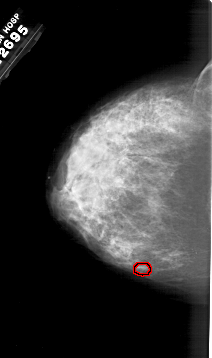

A_1983_1.RIGHT_CC

RIGHT_CC LINES 6481 PIXELS_PER_LINE 3856 BITS_PER_PIXEL 12 RESOLUTION 43.5 NON_OVERLAY

TOTAL_ABNORMALITIES 1

ABNORMALITY 1

LESION_TYPE CALCIFICATION TYPE PUNCTATE DISTRIBUTION CLUSTERED

ASSESSMENT 4

SUBTLETY 1

PATHOLOGY MALIGNANT

TOTAL_OUTLINES 1